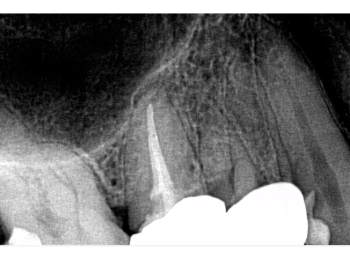

Röntgen Revision 25

Zustand nach Revision 25 und Extraktion 26 und 27.

Röntgen Ausheilung

Zustand nach Ausheilung 25 apikal nach Revision und Regio 26 und 27 nach Extraktion.